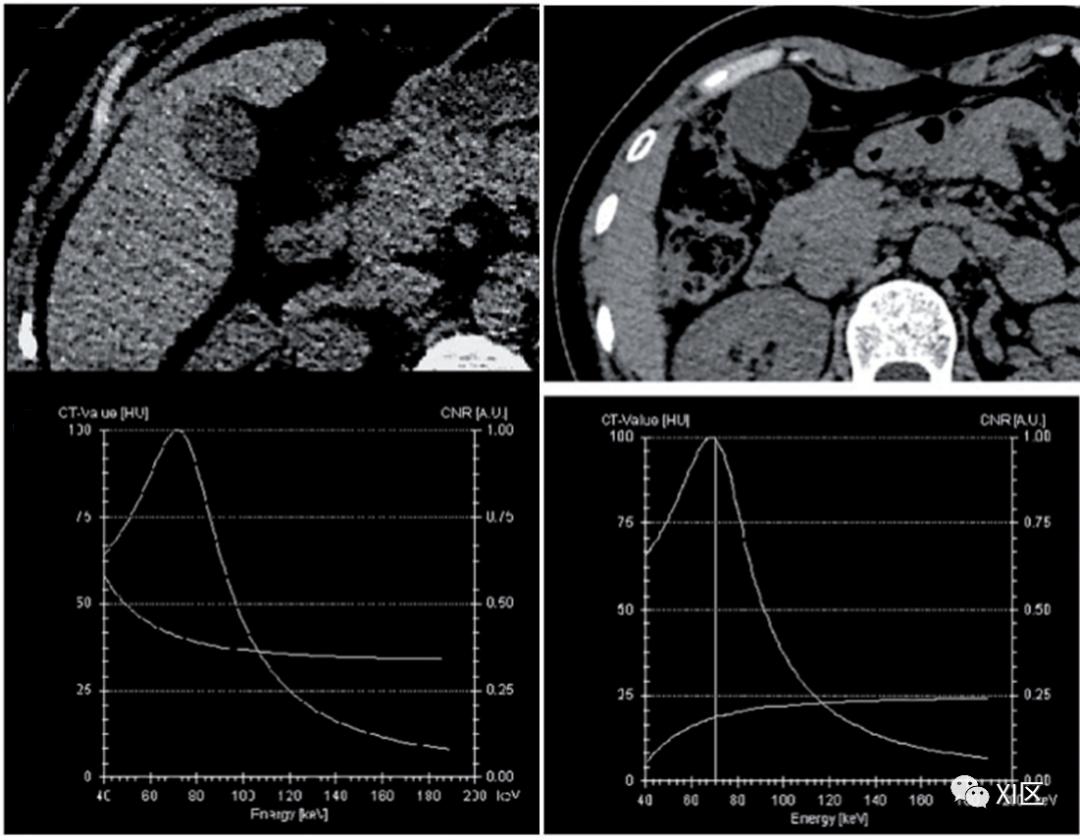

VMIs可用于在工作站上创建能谱曲线。通过在组织中设置感兴趣区域(ROI)并在VMI的每个单色能量(例如,从40到190 keV)下绘制ROI中的平均CT值,获得能谱曲线(图11)。由于曲线的形状随ROI组织中的平均衰减特征而变化,这有助于特定组织类型的表征,并有助于成分分析和获得鉴别诊断。

图11 通过在组织中设置感兴趣的区域并绘制每个单色能量下的平均CT值,可以获得能谱曲线。高原子序数材料的衰减,如碘在较低能量下增加(绿色),水在所有能量下的衰减为零(白色),脂肪在较低能量下的衰减降低(黄色)。软组织以及碘和骨等高原子序数材料的CT值在较低的能量下会增加。水在所有能量下的CT值为零;能量较低时,脂肪的CT值会降低(图11)。当特定组织的ROI曲线模式表明在较低keV下衰减降低时,应考虑存在脂肪。这一观察结果有助于诊断含脂肪疾病,例如富含脂质的斑块、肾上腺腺瘤、胆固醇息肉(图12)和血管平滑肌脂肪瘤。

图12 (左)69岁男子,患有1.5厘米的息肉。平扫CT图像上显示胆囊息肉。能谱曲线显示了在40到190 keV范围内观察到衰减值呈下降状,病理结果表明该病变为腺瘤性息肉。(右)48岁女性,患有1.6厘米的息肉。平扫CT图像上显示胆囊息肉。能谱曲线显示了在40到190 keV范围内衰减值呈上升状,病理结果表明病变是胆固醇息肉。材料分解